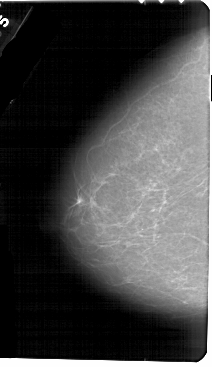

A_1604_1.LEFT_MLO

LEFT_MLO LINES 5491 PIXELS_PER_LINE 3301 BITS_PER_PIXEL 12 RESOLUTION 43.5 NON_OVERLAY